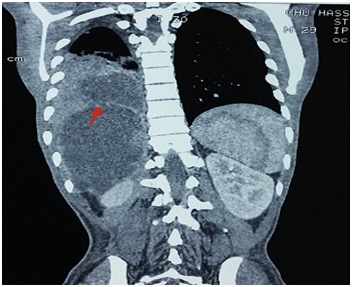

On admission all five patients had an elevated leukocyte count (11.0 to 37.0d 10/L). Two patients had eosinophilia (over 5%). Liver function test results were abnormal in all patients; they had elevated levels of bilirubin, aminotransferases, alkaline phosphatase and γ-glutamyl transpeptidase. The indirect hemagglutination titre for hydatid disease was elevated in all patients (range from 1:412 to 1:1926). Abdominal ultrasonography demonstrated a hydatid liver cyst and different degrees of dilatation of the bile ducts. The CT scan showed a cystic image of the liver appearing to communicate with a pulmonary lesion in two out of our five cases (Figure 1) with patchy densities over the right lung for four patients and for the fifth revealed that the volume of the right hemithorax was diminished with homogeneous density at the basal segments. Cholangiopancreatography endoscopic retrograde (ERCP) revealed dilatation of the biliary tree, communicating with the hydatid liver cysts and helped visualize the Biliobronchial fistula in all patients. Endoscopic sphincterotomy was carried out in all cases. In all our cases, hydatid daughter cysts were impacted in the ampulla of Vater. All patients underwent successful endoscopic sphincterotomy, including removal of daughtercysts (Figure 2). No complications due to endoscopic procedures occurred. After the endoscopic procedure all patients underwent a cyst dome resection, suture of the diaphragmatic defect after hepatodiaphragmatic disconnection by laparotomy.

Figure 1 Thoraco-abdominal computed tomography showing a hydatid cyst of the hepatic dome ruptured in the lung.